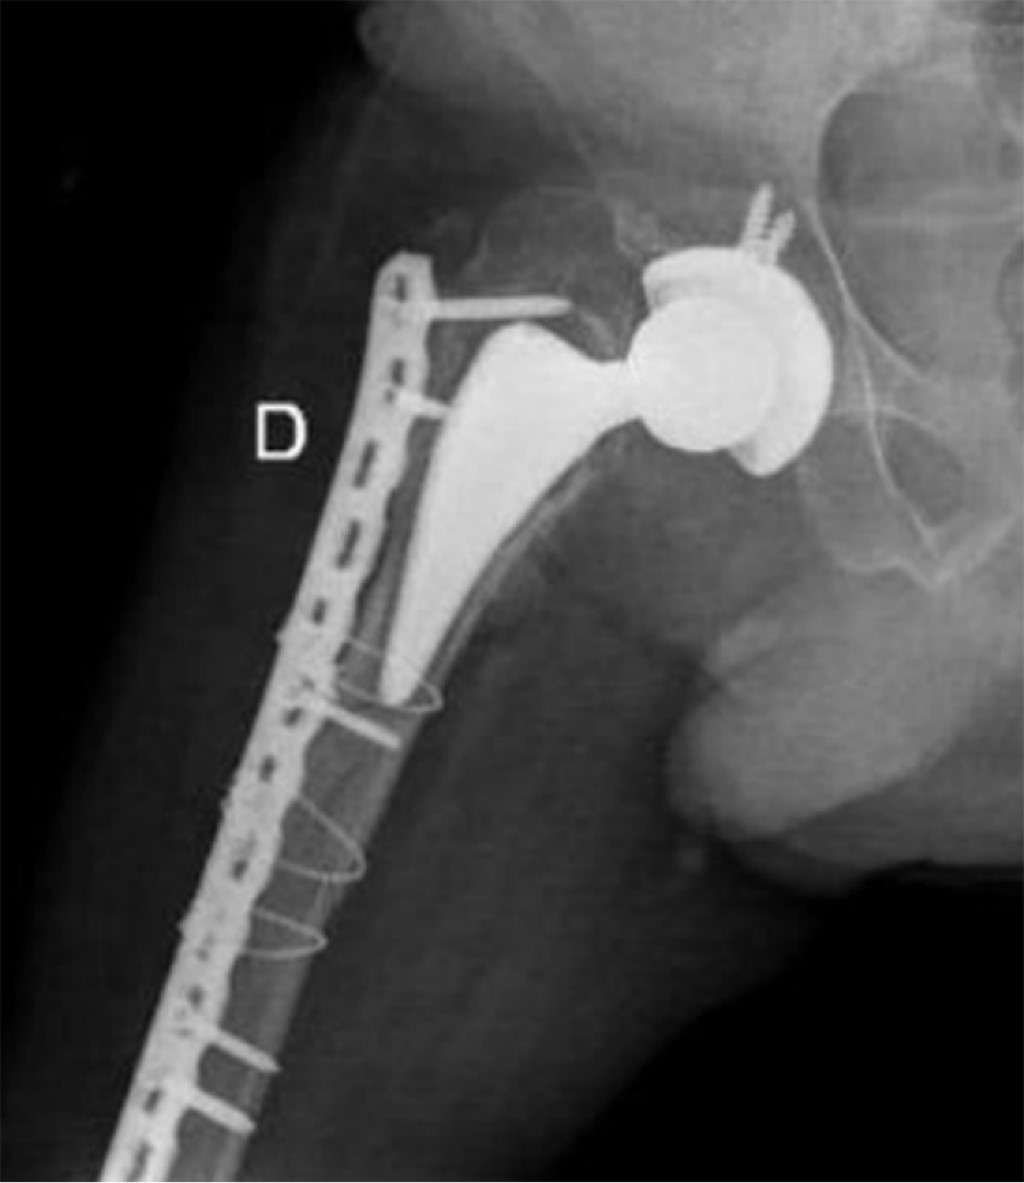

Periprosthetic fracture in a patient with polio sequelae: a case report

Introduction: poliomyelitis paralyzed thousands of children during the 20th century. However, due to mass vaccination its eradication was achieved. Today it is estimated that there are 12 - 20 million people with polio sequelae (PWPS) who make up a risk group for pathological fractures, as a consequence of muscle degeneration and osteopathy. There is no consensus on its treatment. The aim of this report is to demonstrate the problem of fracture management in PWPS. Additionally, an option for the treatment of a periprosthetic fracture in this population is proposed. Presentation of case: 46-year-old male PWPS with pain in the right lower extremity after falling from a chair, with a history of right hip arthroplasty six months ago due to a transcervical fracture. Radiographically, a Vancouver C periprosthetic fracture is seen. Open reduction of the fracture is performed and an anatomical cable-type locking compression plate and cerclage cables are placed. An adequate radiographic evolution is observed. Conclusions: polio is an eradicated disease; however, it should not be ignored since PWPS are a risk group for fractures in pathological terrain. Treatment of these types of fractures and their complications is a challenge. There is a pressing need for comprehensive clinical and surgical guidelines to guide their approach.

Figure 3